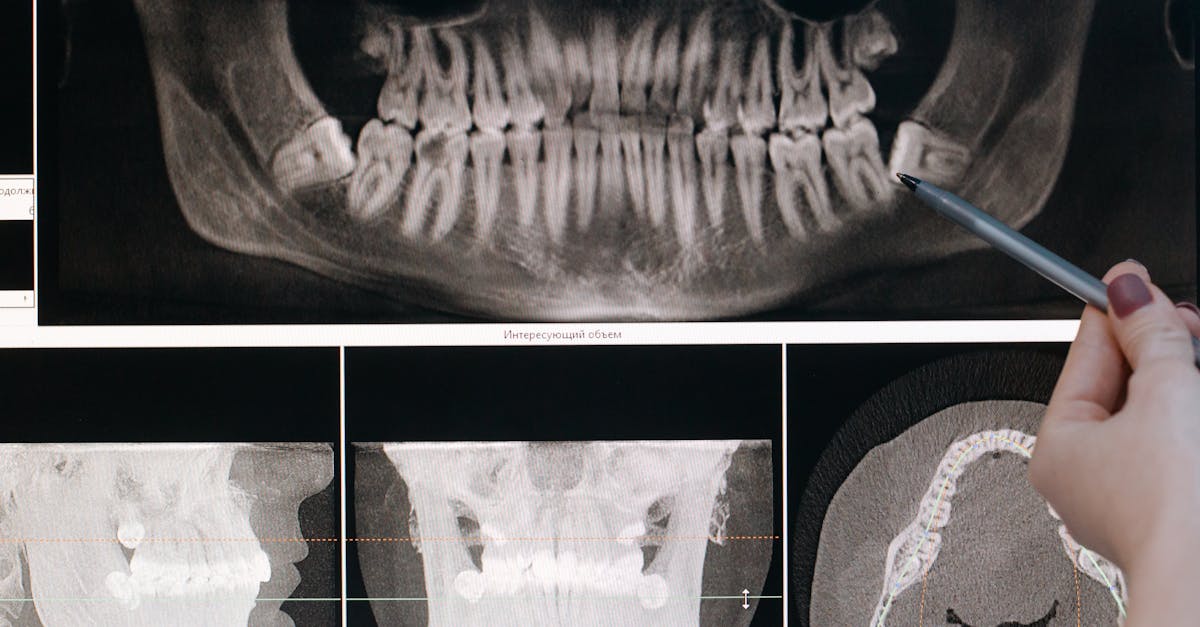

Dr. Resha Sawla is a Consultant Oral and Maxillofacial Radiologist with expertise in CBCT-based diagnostics, having interpreted over 14,000 CBCT scans in the last decade across a wide range of clinical indications including endodontics, implant planning, maxillofacial pathology, temporomandibular joint disorders, sinus evaluation, orthodontic assessment, trauma, and developmental anomalies.

Dr. Resha has been associated with leading diagnostic centers across India in both in-house and remote consulting roles, offering structured CBCT and panoramic radiology reporting, complex case discussions, and second-opinion reviews where needed. Her reports prioritize diagnostic accuracy, clarity, ethical standards, and clinically relevant insights delivered with a timely turnaround, facilitating seamless interdisciplinary care.